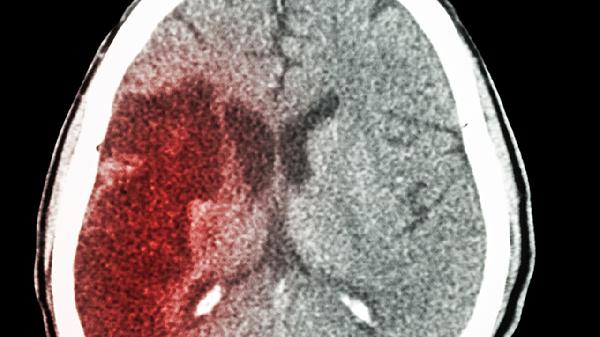

当出血部位位于丘脑、基底节区或小脑时,血肿可能直接压迫中脑、脑桥等脑干结构。这类患者除意识障碍外常伴随瞳孔变化、呼吸节律异常等生命体征改变。需通过头颅CT明确出血位置,必要时行脑室穿刺引流或血肿清除术。

出血后72小时内血管源性脑水肿逐渐加重,可进一步扩大脑损伤范围。表现为意识障碍程度进行性加深,影像学检查可见低密度水肿带。除脱水治疗外,可选用甲泼尼龙琥珀酸钠注射液控制炎症反应,必要时采用亚低温治疗。